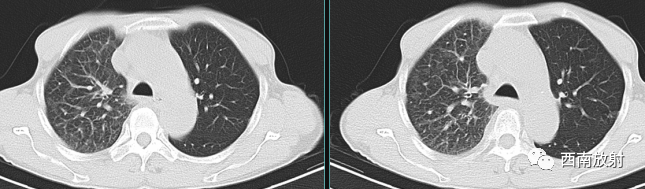

脑转移瘤:多位于灰、白质交界处,多呈长T1、长T2信号,而淋巴瘤多呈低或等T1、等T2信号;注射对比剂后,转移瘤多呈结节状明显强化,病灶较大者中心常有坏死,这在淋巴瘤相对少见;转移瘤周边水肿明显,一些患者有中枢神经系统以外肿瘤病史。

▲病例:女性,66岁,右肺肺腺癌病癌性淋巴管炎,脑转移瘤,脑内多发类圆形结节影,明显强化。